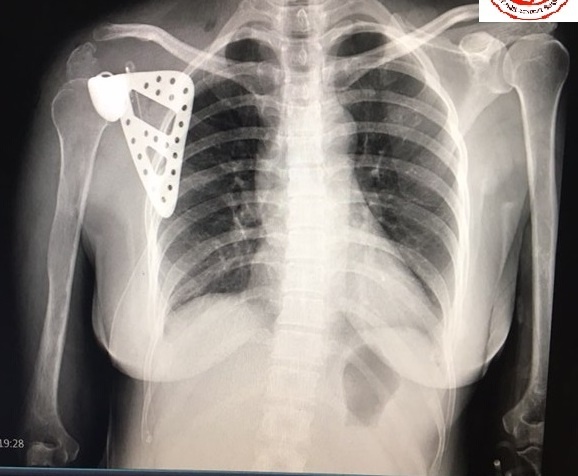

Hình ảnh X-quang xương bả vai sau phẫu thuật. Ảnh: Sức Khỏe Đời Sống.

Qua 5 ngày điều trị, hiện tại cô Th. đã hoàn toàn khỏe mạnh, đã cử động được phần cẳng tay và bàn tay bình thường, vết mổ hoàn toàn khô, không có dịch, chụp Xquang kiểm tra thấy xương bả vai nhân tạo hoàn toàn đúng vị trí giải phẫu, chưa phát hiện các biến chứng nghiêm trọng nào, cô Th hoàn toàn hài lòng với ca phẫu thuật.